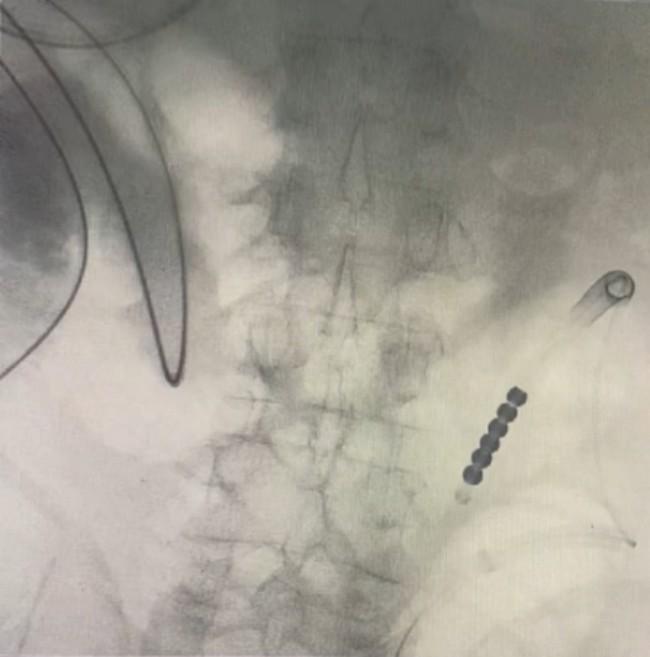

患者在医院急救中心就诊,胃肠外科主任医师王金申、郑春宁评估后,制定了以置入肠梗阻导管并进行药物溶石为主的保守治疗方案。消化内科主任医师李宾及护理团队连夜在胃镜与X线引导下,将导管精准放置至结石近端,引流肠液并注入碳酸氢钠溶液进行溶石。次日,患者入院接受进一步治疗。

经结肠梗阻导管造影术